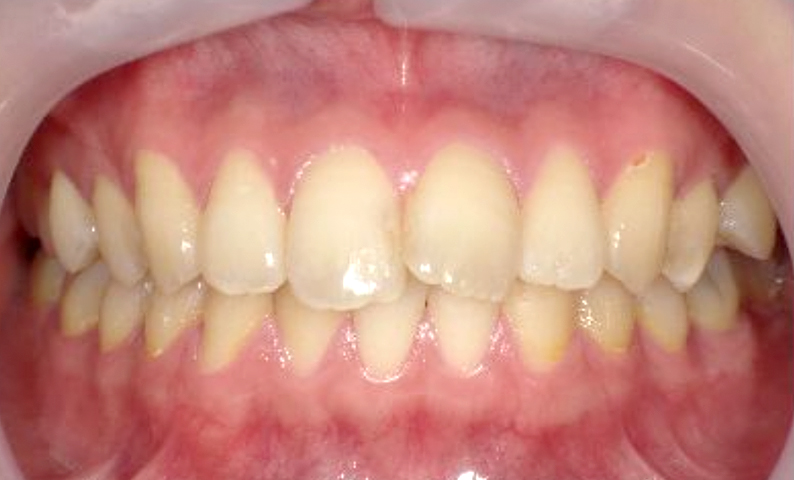

症例_006 前歯「捻転歯」症例

治療期間:7ヶ月金額:30万円+税20代女性少しのねじれ歯の形態修正上の前歯だけ

| Before | After |